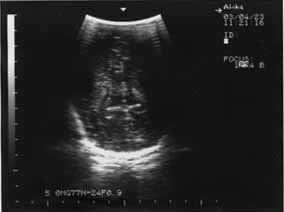

У остальных новорожденных, из группы детей получающих Лецитин, выявлена положительная ультразвуковая динамика процесса в головном мозге в виде уменьшения эхоплотности в перивентрикулярном пространстве, которое свидетельствовало об ишемическом страдании. Структуры мозга становились более четкими, а к концу первого месяца жизни исчезали очаги глиоза и мелкие кисты, нивелировались участки уплотнения борозд (рис. 3,4,5,6,).

|

Рис. 5 Срок гестации 28 недель. | Рис.6. На 10-е сутки от начала лечения. В динамике отмечается уменьшение интенсивности п/в ишемии. |